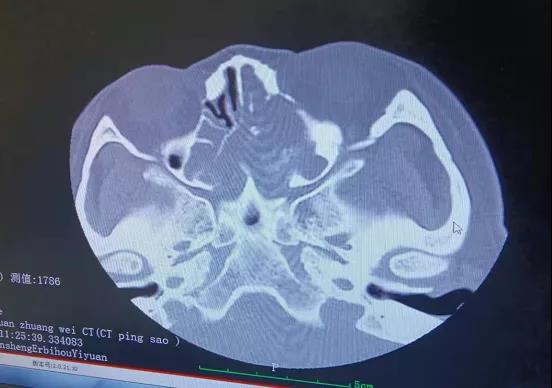

接诊后,张思叶主任第一时间给患者做了详细地检查,发现患者左侧中鼻道有一半透明荔枝样新生物堵塞鼻孔,同时双侧下鼻道大量脓性分泌物,CT显示:鼻窦内部可见到颗粒状或斑点状高密度影,内有钙化灶,鼻窦内侧壁受压向中线移位,鼻中隔骨质连续性中断、变形,提示鼻腔及鼻窦占位性病变。

鼻窦内部可见不规则软组织密度影

其中有斑点状钙化影,伴窦壁骨质增生及骨质破坏。

乍一看,符合肿瘤的表现,但郑州民生耳鼻喉医院张思叶主任仔细询问病史,患者左侧上颌牙有龋齿和疼痛的症状,根据多年经验以及病人临床表现和CT扫描结果综合判断,病人得的很可能是:霉菌性鼻窦炎,也就是说,霉菌长到了鼻子里。但也不排除鼻窦肿瘤的可能。需要手术治疗。